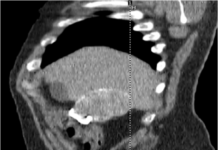

On the PA view, the cardiac borders are smaller and more defined. Given the way the x-ray beam works, the heart appears smaller and with sharper borders on the PA view. The reason is that the patient’s chest (anterior) is against the x-ray film with the beam entering from posterior (P) to anterior (A) – hence the term “PA.” Similarly, the AP view is when the beam enters from front to back with the x-ray film at the back of the patient – therefore, the heart is magnified and the margins are minimally less sharp.